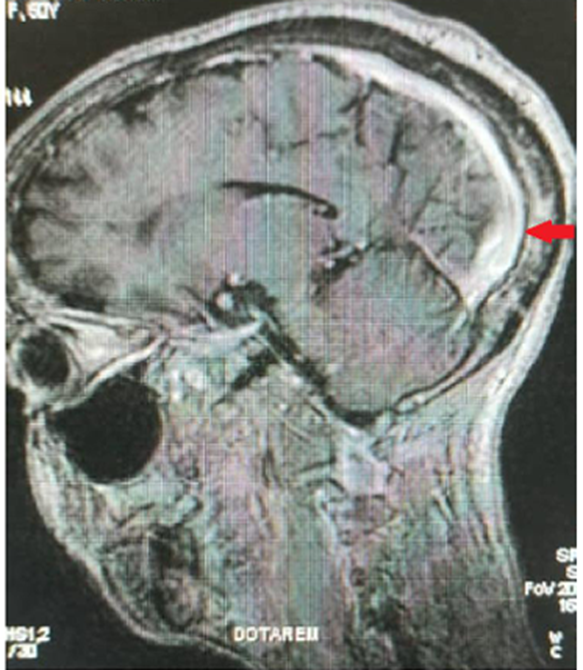

A 50 years old woman with SS homozygous SCD diagnosed in her childhood, but lost to follow-up, was admitted in the internal medicine department of the Garoua general hospital. She presented with worsening headaches, associated with a generalized tonic-clonic seizure which occurred one day before admission. The history revealed that the patient had received a blood transfusion for anemia, five days earlier. Physical examination showed left facial palsy and a left pyramidal syndrome with 4/5 muscle power. A head CT-scan was done showing diffuse cortical atrophy. We pushed the investigations further by performing a magnetic resonance angiography which showed a thrombosis of the superior sagittal sinus (figure 1). Laboratory workups showed normocytic normochromic anemia with 8.5 g/dl of hemoglobin. Basic hemostasis tests were normal. HIV and hepatitis B and C serologies were negative. Serum creatinine was 169mg/dl (glomerular filtration rate = 41.31ml/mn/1.73m2) and the natremia was 159mmol/L. Thyroid function tests revealed a hypothyroidism with a TSHus of 1.008 UI/mL, FT4 of 1.61pmol/L and FT3 of 9.881pmol/L. Thrombophilia and immunological investigations were not done because of timing and logistical constraints. The patient was treated with low molecular weight heparin switched with acenocoumarol (target INR 2-3), carbamazepine 200mg bid, nefopam 10mg tid, levothyroxine 25µg od, and hydration with crystalloids (1500mL/day). The outcome was favorable with amendment of headaches, seizures, and normalization of kidney function and natremia.

Figure 1: Cerebral magnetic resonance angiography showing the thrombosis of the superior sagittal sinus (red arrow)